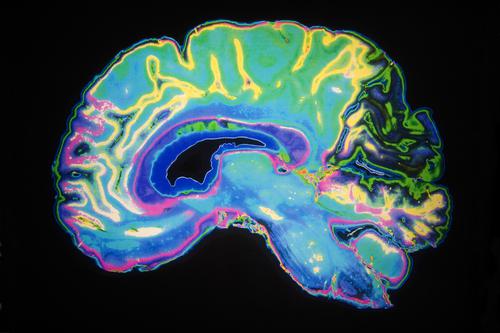

Les neuroscientifiques britanniques ont utilisé l’imagerie par résonance magnétique (IRM) pour étudier le cerveau de 300 adolescents et jeunes adultes de 14 à 24 ans. En comparant la structure cérébrale des jeunes participants à différents âges, ils ont découvert que la couche extérieure du cerveau, le cortex, s’affine durant l’adolescence. En parallèle, la quantité de myéline, une substance qui entoure les axones des neurones pour les protéger, augmente dans cette zone cérébrale. Des observations surprenantes.

De fait, jusqu’à maintenant la littérature scientifique laissait penser que la myéline était majoritairement présente dans la substance blanche, région où les prolongements des neurones se concentrent, permettant d’accélérer la transmission d’informations dans le cerveau et la communication entre les différentes régions cérébrales. Or, ces récents travaux montrent que la myéline est retrouvée dans la substance grise, et ce dans des quantités importantes à l’adolescence.

« Durant nos jeunes années, notre cerveau continue à se développer. Quand nous sommes des enfants, ces changements sont considérables, tandis qu’à l’adolescence les modifications peaufinent les détails, explique le Dr Kirstie Whitaker du département de psychiatrie de l’université de Cambridge, et l’un des auteurs de l’étude. Les nœuds de connexions entre les différentes régions cérébrales se mettent en place alors que les plus importantes connexions se renforcent. Nous pensons que ce sont dans ces zones que la myéline augmente à l’adolescence ».

Selon les observations des chercheurs, ces modifications concernent surtout les régions chargées de pensées complexes ou de la prise de décision. Celles-ci pourraient expliquer les profonds bouleversements d’humeur et de comportement vécus par les adolescents.